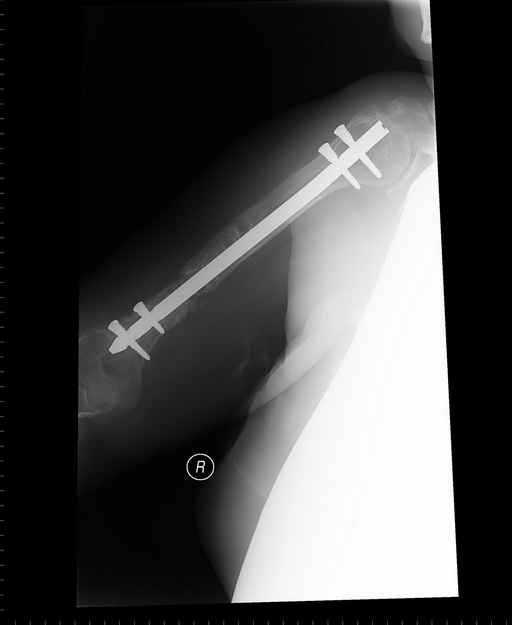

Больная 48 лет, медсестра-массажист, перелом плеча 7 лет назад, оперирована 4-кратно и безуспешно

Больная 48 лет, медсестра. Травма получена 7 лет назад, оперирована первично в Турции - остеосинтез пластиной - несращение - реостеосинтез стержнем там же через год (обычным, с выстоянеием его в полость плеча) - несращение - поступила к нам впервые в марте 2008 года - удаление стержня, реостеосинтез пластиной и костная пластика, в течение 2 лет лизис кости вокруг винтов, смещение фиксатора, в марте 2010 - удаление пластины, реостеосинтез интрамедуллярным стержнем с блокированием (рассверливание + костная пластика). В динамике - вновь лизис в области перелома, нестабильность дистальных блокирующих винтов.